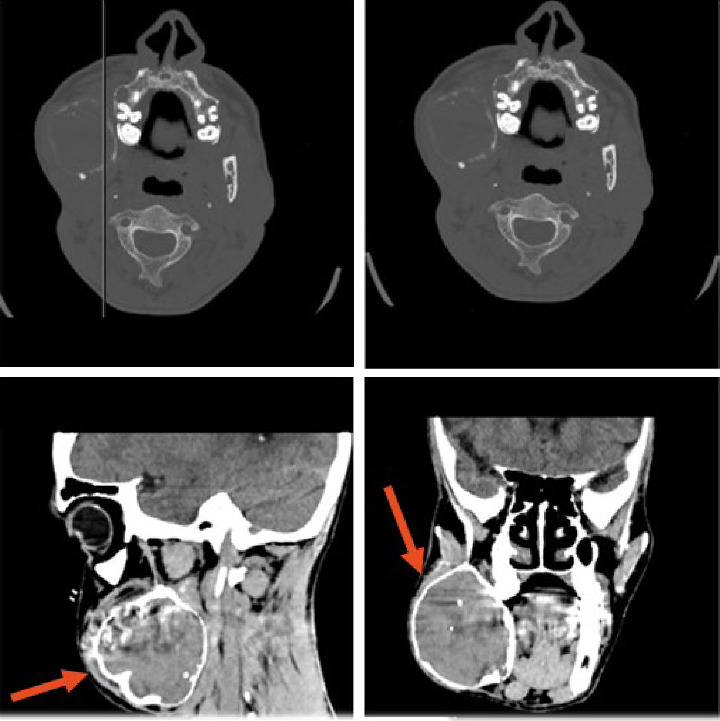

大多数原发性甲状旁腺功能亢进(PHPT)是散发性的,由甲状旁腺瘤引起。遗传性形式可能发生在高达10%的PHPT患者中,更常见于年轻患者。甲状旁腺功能亢进-下颌肿瘤(HPT-JT)综合征的特征是高达95%的患者有PHPT, 25%-50%的患者有颌骨骨化纤维瘤。我们描述的情况下,35岁的男性从孟加拉国转介到我们医院,由于一个巨大的右下颌骨肿胀:一个罕见的非骨化纤维瘤下颌骨被诊断。由于功能性阳痿,左肩磁共振成像(MRI)显示肱骨近端多分叶囊肿样病变,诊断为棕色肿瘤(BT)。随后的测试突出高钙血症和低磷血症与高甲状旁腺激素水平。鉴定出CDC73的杂合致病变异c96 >a p.Trp32Ter。据我们所知,这是第一例与CDC73致病变异相关的HPT-JT综合征,与手臂的BT和罕见的下颌骨非骨化纤维瘤相关。

Most cases of primary hyperparathyroidism (PHPT) are sporadic and are caused by parathyroid adenomas. Hereditary forms may occur in up to 10% of PHPT patients and are more frequent in younger patients. The hyperparathyroidism-jaw tumor (HPT-JT) syndrome is characterized by PHPT in up to 95% of patients and ossifying fibromas in the jaw in 25%-50%. We describe the case of a 35-year-old male from Bangladesh referred to our hospital due to a voluminous right mandibular swelling: a rare nonossifying fibroma of the mandible was diagnosed. Due to functional impotence, a left shoulder magnetic resonance imaging (MRI) was performed with evidence of a pluri-lobulated cyst-like lesion in the proximal humeral area diagnosed as a brown tumor (BT). Subsequent tests highlighted hypercalcemia and hypophosphatemia with high PTH levels. A heterozygous CDC73 pathogenic variant c.96>A p.Trp32Ter was identified. To the best of our knowledge, this is the first reported case of HPT-JT syndrome related to a CDC73 pathogenic variant, associated to a BT of the arm and a rare nonossifying fibroma of the mandible.